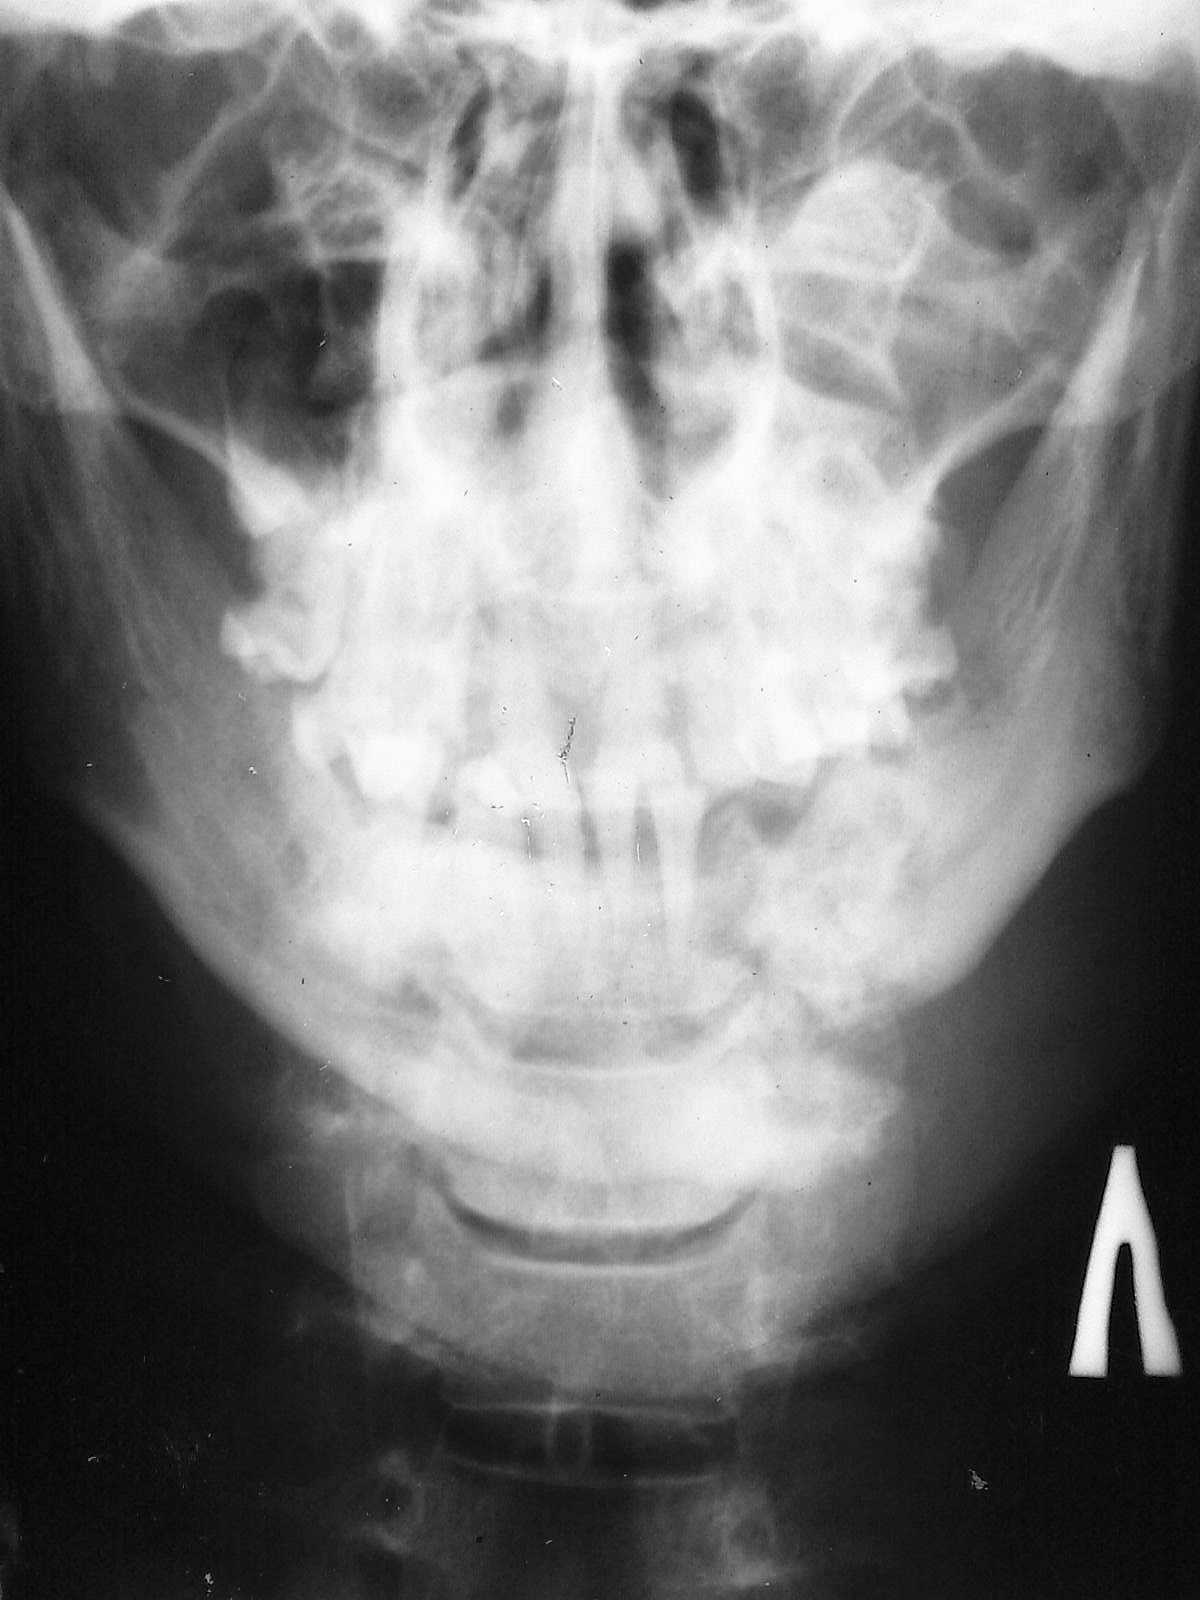

А это визави.

А у нас так ломают челюсти

Зашинировали

У этого 3 г. назад нелеченная травма, теперь остеомиелит